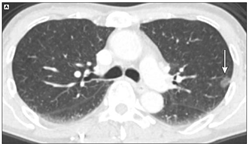

良性病因 - 良性肺结节的常见原因包括感染性肉芽肿(如图4)和良性肿瘤,如肺错构瘤(如图5)。不太常见的原因包括血管(如图6)和炎症性病变。

图4 感染性肉芽肿(说直白些就是一种感染,大多吃吃抗生素就好了)

图5 肺错构瘤(软骨、脂肪等长错了位置)

图6 血管性病变(数龙戏珠)